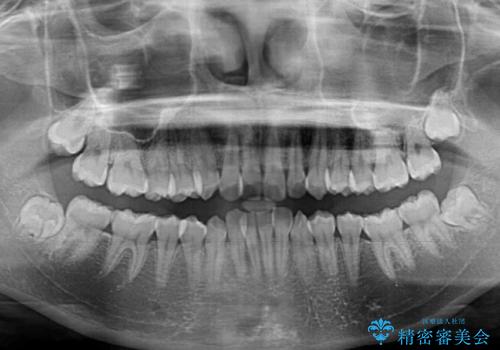

前歯のデコボコと隠れてしまう下顎前歯 インビザラインですっきりと改善

- 前歯のデコボコと、深い咬み合わせにより前歯が隠れていることを気にして来院された患者様です。

海外に長期滞在する予定があるとのことで、インビザラインにて矯正治療を行うこととしました。

インビザライン発注後に長期滞在先から2年間ほど帰国することができず、インビザラインの有効期限内に終了できるのか不安でしたが、矯正治療開始後は十分な装着時間を達成され、1年未満の期間で無事に終えることができました。